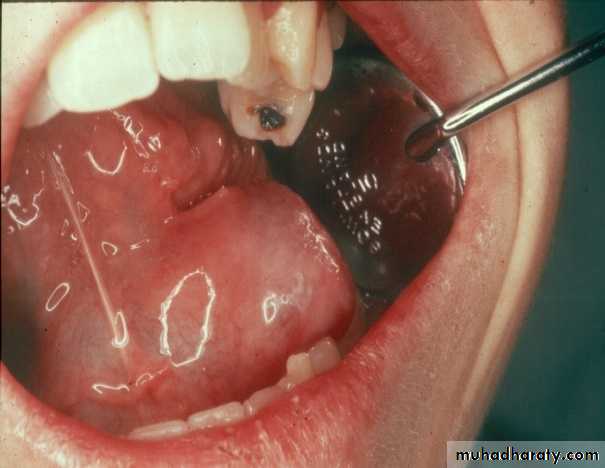

RanulaSublingual salivary gland mucocele

Treatment should include removal of Sublingual gland